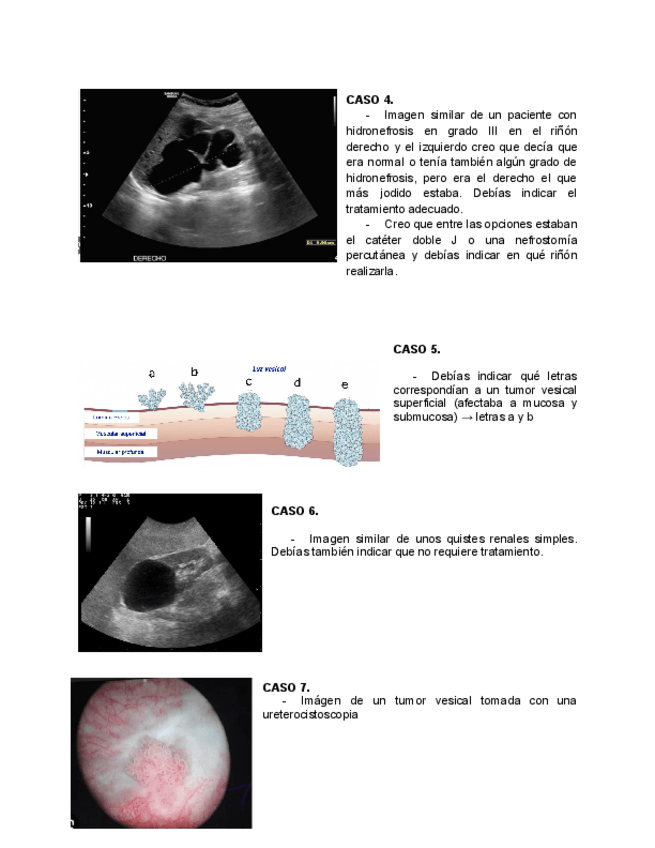

He publicado nuevos apuntes de 4º Nefrologia y Urología: Examen-practico-urologia-2025.pdf